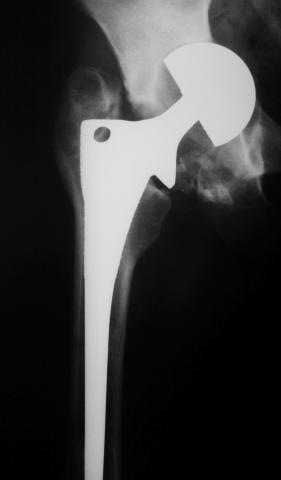

Лечился в стержневом аппарате по месту жительства. АВФ демонтировали через полгода из-за воспаления в области стержней (рис 2). После демонтажа в течение месяца больной лихорадил до 38*, были боли в бедре. Эти явления исчезли после курса антибиотиков. Через год после травмы в ЦРБ ему имплантировали биполярный протез (рис 3). Рана зажила первично. Ходил с костылями, слегка приступая на ногу. На контрольных осмотрах выявлена прогрессирующая протрузия (рис 4-6).